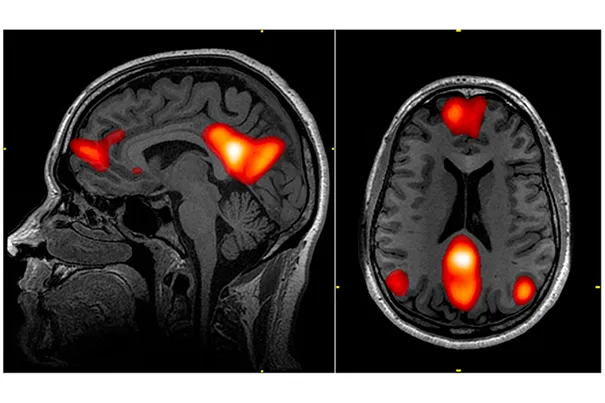

آزمایش جان-دیلن هینز (John-Dylan Haynes): با استفاده از فناوریهای جدیدتر مانند fMRI، دانشمندان این ایده را یک قدم فراتر بردند. در آزمایشهایی که در موسسه ماکس پلانک انجام شد، تیم دکتر هینز توانست با تحلیل فعالیت مغزی افراد، با دقت قابل توجهی پیشبینی کند که آنها کدام دکمه (چپ یا راست) را فشار خواهند داد، آن هم تا ۷ الی ۱۰ ثانیه قبل از اینکه خودشان آگاهانه تصمیم بگیرند!